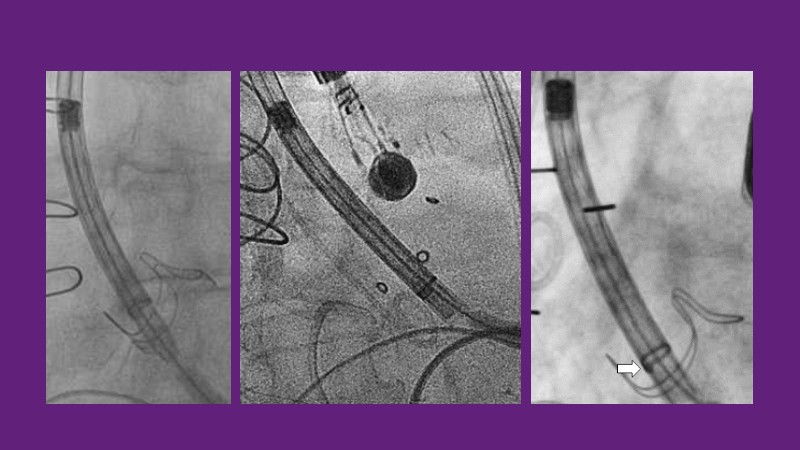

Don’t miss this PCR Tokyo Valves 2025 session replay, where leading experts share key techniques for simplifying and optimising TAVI procedures with the Evolut device. This session covers essential insights into safely performing procedures on patients with various anatomical types using the self-expandable valve, while emphasising the importance of long-term patient care and outcomes. Discover valuable strategies for surgical explantation of transcatheter aortic bioprostheses, coronary cannulation, and commissural alignment post-TAVR. Learn expert tips for streamlining procedures, such as semi-rapid pacing, using Dryseal long, and skipping pre-BAV to improve TAVI results. Watch now to stay ahead in the field!

- To understand simple procedure as semi-rapid pacing, using Dryseal long and skip pre-BAV